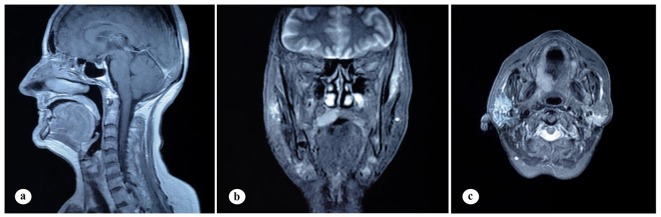

A 61-year-old woman was admitted to the Department of Otolaryngology with a 1-year history of swelling in the right palatal region and problems with pronunciation and chewing. Also, she suffered from a painless, progressively enlarging mass in the right preauricular region. On physical examination, swelling of the right parotid gland (Fig. 1a) and a 2 × 2.5 cm mass with central ulceration on the right hard palate (Fig. 1b) were noted. She had no history of fever, weight loss or night sweats. No lymph nodes were palpated in the head and neck region. Blood count was as follows: hemoglobin 13 g/dL, total leukocyte count 6,240/mm3 (neutrophil 54%, lymphocyte 36%) and platelet 185,000/mm3. Biochemical tests showed normal lactate dehydrogenase (LDH), beta-2 microglobulin levels and protein electrophoresis were normal. Cervical magnetic resonance imaging (MRI) confirmed a 2 × 2.5 cm mass on the right side of the hard palate and a 2.5 × 3.5 cm mass in the right parotid gland region (Fig. 2a, b and c). Incisional biopsy of the palatal mass revealed subepithelial infiltration of atypical centrocyte-like cells with or without clear cytoplasm that stained for CD20 and kappa light chain, and did not stain for CD5, CD10, CD23 and lambda light chain, suggesting marginal zone B-cell lineage (Fig. 3a, b). Further examination included hepatitis B, C, HIV testing, chest and abdominopelvic computed tomography (CT), bone marrow aspirate and biopsy, and gastroscopy with multiple biopsies, all of which revealed unremarkable findings. The final diagnosis was MALT lymphoma with involvement of two extralymphatic sites: parotid gland and hard palate. Screening for autoimmune disorders including Sjogren’s syndrome was negative. Because of multiple extranodal involvements, a multi-agent chemotherapy regimen, rituximab, cyclophosphamide, doxorubicin, vincristine, and methylprednisolone (R-CHOP) was started. After five cycles, the patient had improved quality of life through the recovery of orofacial functions such as pronunciation and chewing. After six cycles, mass arising from the right side of the hard palate almost totally disappeared and the ulceration totally regressed (Fig. 4a). Also, swelling on the right parotid gland significantly regressed. MRI confirmed the disappereance of the mass in the right palatal region (Fig. 4b) and the marked regression of the enlargement of the right parotid gland. Chemotherapy was completed up to eight cycles. She has been in complete remission (CR) without any evidence of recurrent lymphoma infiltration for the past 44 months.

Figure 2.

Findings on cervical MRI. (a) Isointense mass lesion on the hard palate on sagittal, T1-weighted plane. (b) Mass lesion on the right side of the hard palate on coronal, T1-weighted, fat-saturated, contrast-enhanced sequence. (c) Mass lesion in the right parotid gland on axial, T1-weighted, contrast-enhanced plane.